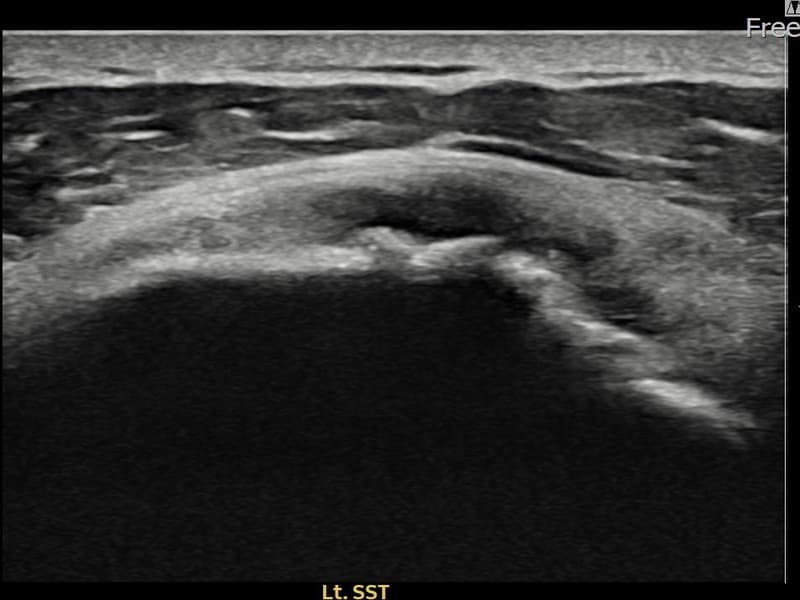

超音波検査にて左 棘上筋腱 광범위 部分断裂(15mm × 6mm (腱厚の約70%欠損))を確認。縫縮術施行後、腱の連続性が回復し、日常生活に復帰されました。

施術前

術前超音波にて左 棘上筋腱 광범위 部分断裂・左肩棘上筋腱のエコー不連続と腱欠損(15mm × 6mm (腱厚の約70%欠損))を確認。術後超音波では断裂部位が再生組織で充填され、腱の連続性回復とエコーパターンの正常化が確認されました。